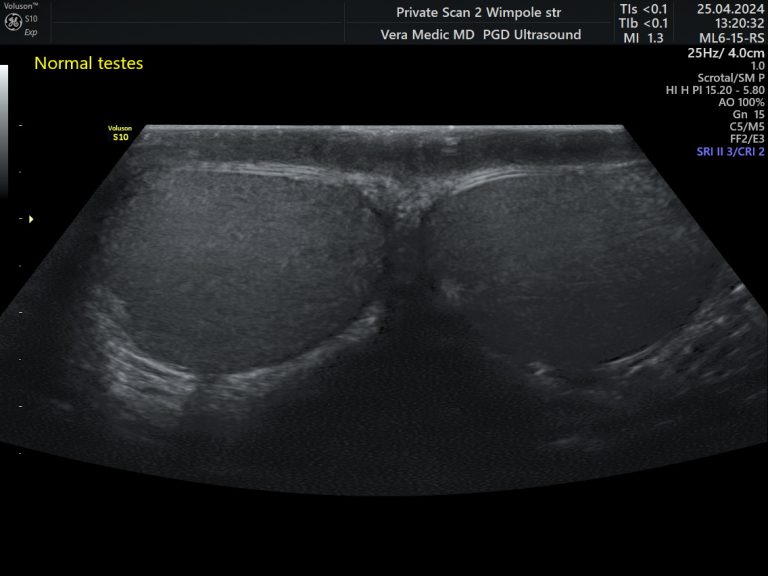

• Testicles

Testicles Scan is done externally and no preparation is required.